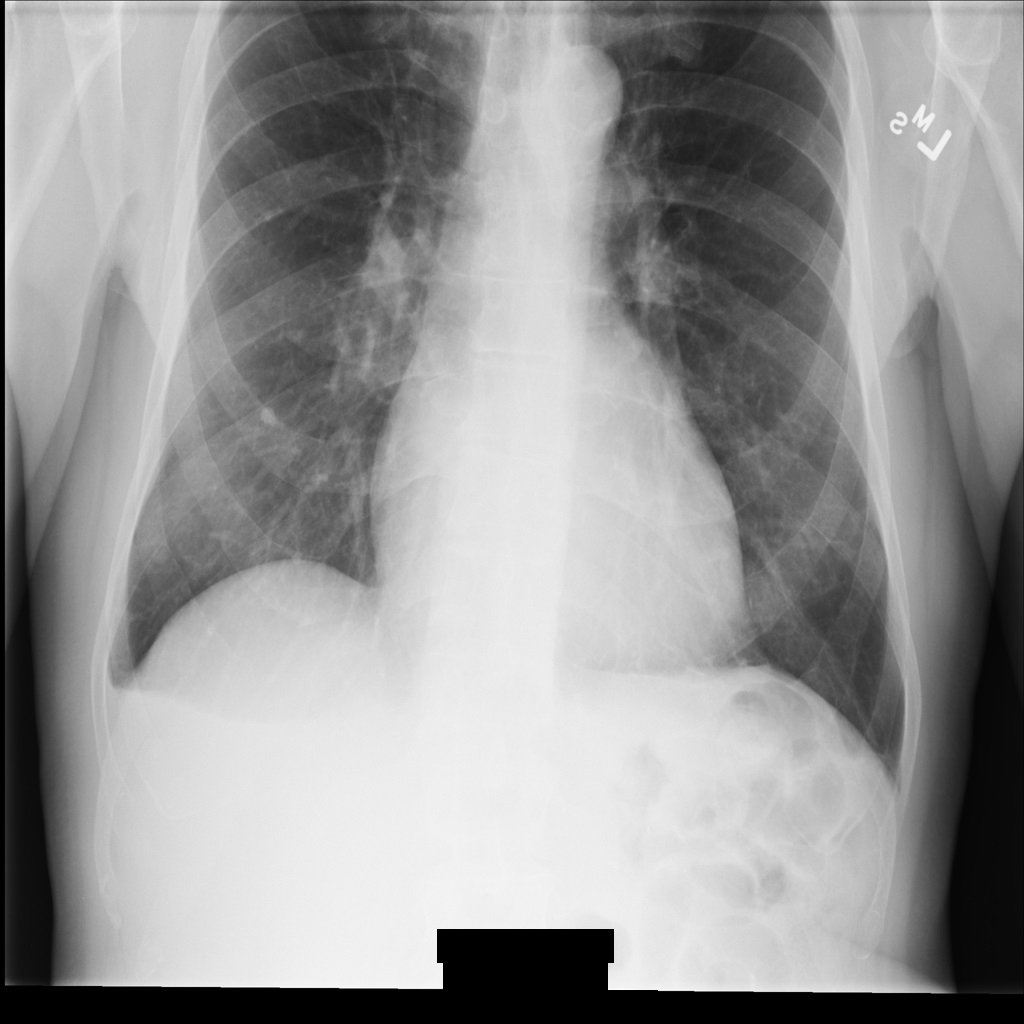

サンプル画像

このページの一部のサンプルには、匿名化された画像の出力が含まれています。各例では、入力として以下の元画像を使用しています。各匿名化オペレーションからの出力イメージをこの元のイメージと比較して、オペレーションの効果を確認できます。

REDACT_ALL_TEXT を使用して画像を匿名化すると、画像は次のようになります。画像の下部にある焼き付きテキストがすべて秘匿化されていることに注目してください。

REDACT_ALL_TEXT を使用して匿名化された後の DICOM インスタンス。Clean Descriptors オプションを使用して機密テキストを秘匿化する